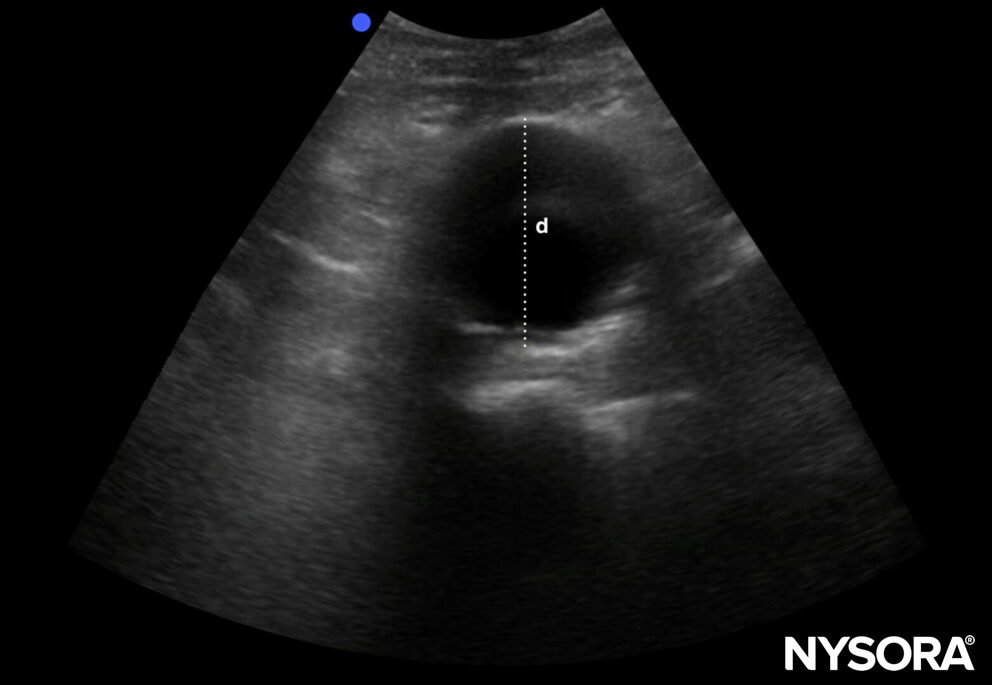

AAAs have a diameter of ≥ 3 cm

Diameter of an AAA: ≥ 3 cm.

- Iliac arteries ≥ 1,5 cm are abnormal

- The risk of rupture increases with the diameter of the aneurysm.

- AAAs of ≥ 5,5 cm have an increased risk of rupture and should be considered as an emergency. (co-existing other pathology, such as Marfan’s disease, decreases the risk cut-off to < 5 cm)